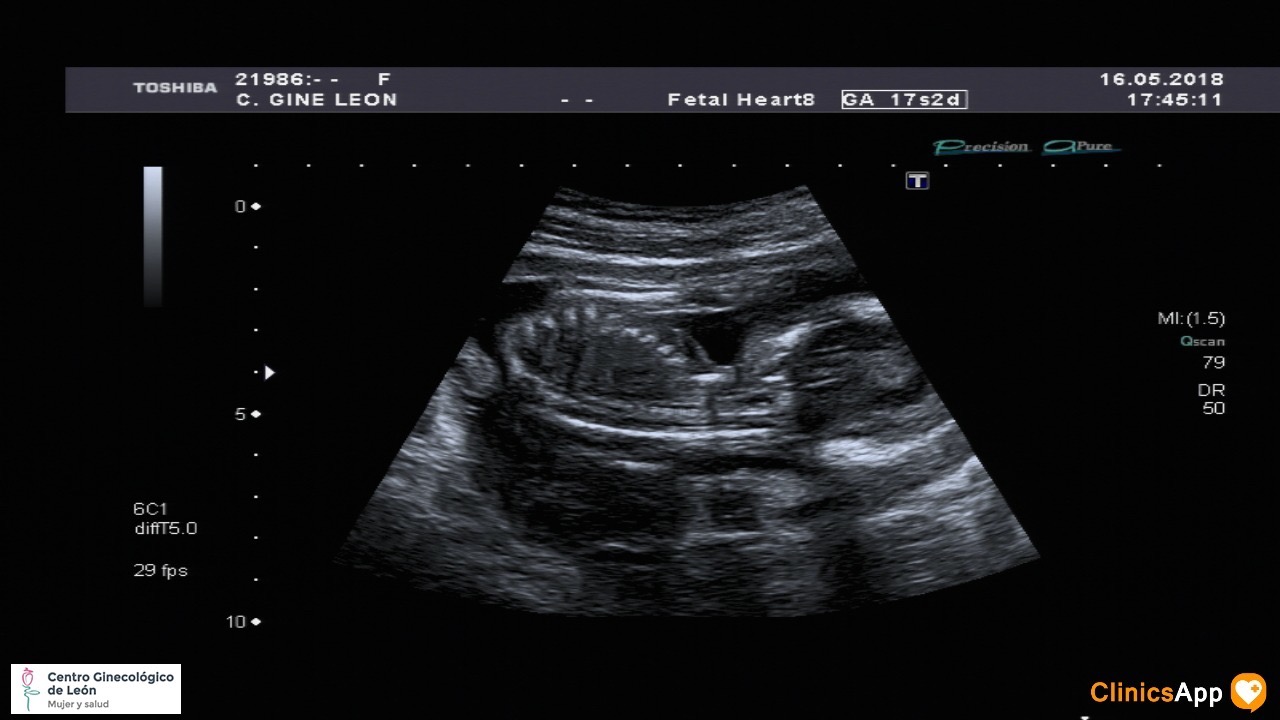

Ecografías de hoy